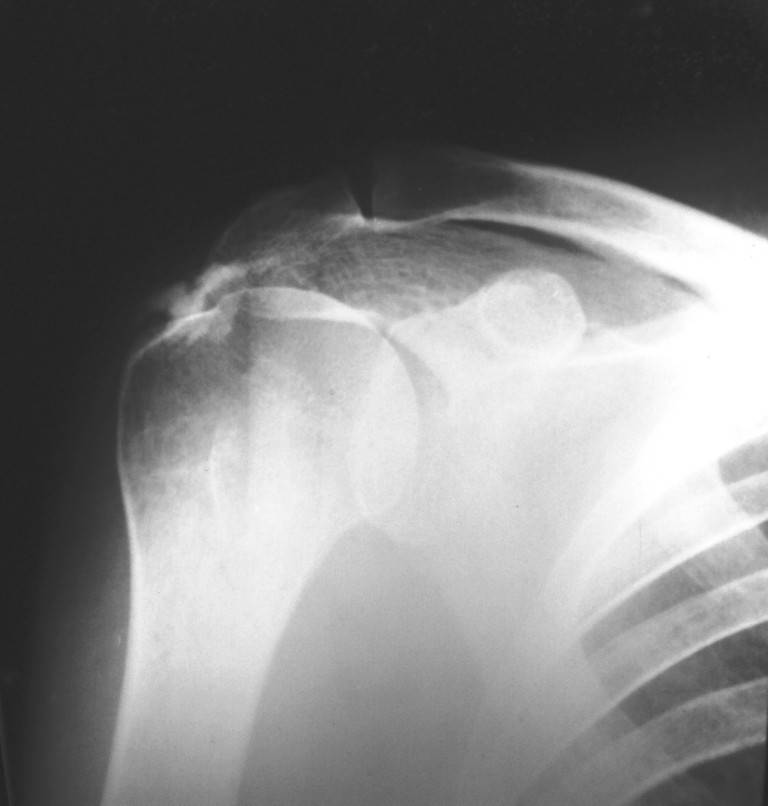

Снимок проводился с целью контроля. Больная обратилась по поводу аналогичного процесса только в левом плече. Я попросил сделать снимок также и правого сустава, так как лечил её в 2003г. с аналогичным диагнозом, но только с правой стороны.

По вашей просьбе размещаю снимок 2003г.